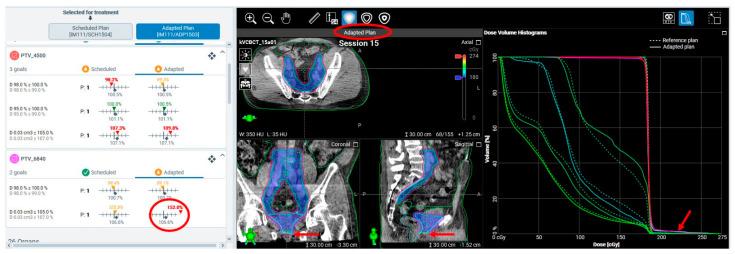

Cone-beam computed tomography (CBCT)-guided online adaptive radiotherapy (oART) represents a significant advancement in radiation oncology, enabling on-couch plan adaptation to account for daily anatomical changes. While this automation improves precision and workflow efficiency, it also introduces new failure modes (FMs) and workflow irregularities. This study aimed to systematically evaluate the clinical and technical challenges associated with CBCT-guided oART implementation. We retrospectively analyzed over 1000 CBCT-guided oART sessions for pelvic malignancies performed at our institution. A multidisciplinary team conducted a comprehensive review to identify and classify FMs, followed by root cause analysis (RCA) to evaluate their impact on treatment safety, efficacy, and workflow robustness. In addition to session-terminating FMs, we identified recurring failure modes across three major domains: (1) system-driven issues, such as rigid target localization and software-driven irregularities; (2) patient-driven challenges, including interfractional and intrafractional anatomical variations; and (3) treatment planning and execution failures, including excessive dose hotspots from field-of-view limitations. The system's closed-loop automation, while streamlining processes, introduced rigid constraints in plan adaptation and fallback plan execution, occasionally leading to unintended dose discrepancies. This study provides a comprehensive clinical practice-based evaluation of CBCT-guided oART, highlighting system-specific failure modes and their implications. Addressing these challenges requires structured quality assurance processes, multidisciplinary collaboration, and continuous workflow refinement. Our findings contribute to the development of safer and more robust adaptive radiotherapy platforms and clinical workflows.

锥形束计算机断层扫描(CBCT)引导的在线自适应放射治疗(oART)是放射肿瘤学的一项重大进展,能够在治疗床上对计划进行调整,以适应每日的解剖结构变化。虽然这种自动化提高了精度和工作流程效率,但也引入了新的故障模式(FMs)和工作流程异常情况。本研究旨在系统评估与CBCT引导的oART实施相关的临床和技术挑战。我们回顾性分析了在我们机构进行的1000多例针对盆腔恶性肿瘤的CBCT引导的oART治疗疗程。一个多学科团队进行了全面审查,以识别和分类故障模式,随后进行根本原因分析(RCA),以评估它们对治疗安全性、疗效和工作流程稳健性的影响。除了导致疗程终止的故障模式外,我们还在三个主要领域识别出了反复出现的故障模式:(1)系统驱动的问题,如刚性靶区定位和软件驱动的异常情况;(2)患者驱动的挑战,包括分次间和分次内的解剖结构变化;(3)治疗计划和执行失败,包括由于视野限制导致的过量剂量热点。该系统的闭环自动化在简化流程的同时,在计划调整和备用计划执行方面引入了刚性约束,偶尔会导致意外的剂量差异。本研究基于临床实践对CBCT引导的oART进行了全面评估,突出了特定系统的故障模式及其影响。应对这些挑战需要结构化的质量保证流程、多学科协作以及持续的工作流程优化。我们的研究结果有助于开发更安全、更稳健的自适应放射治疗平台和临床工作流程。